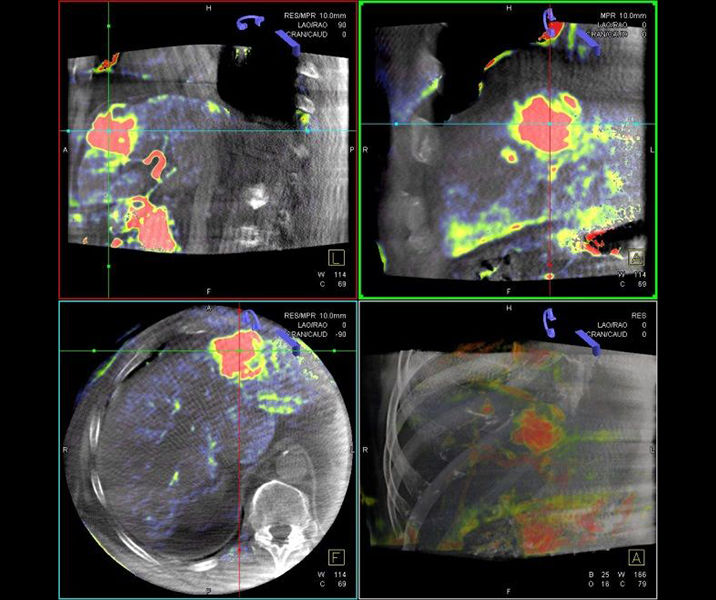

Abbildung: Bei der perkutanen Thermoablation von Lungentumoren werden spezielle Applikatoren unter CT-Bildgebung in den Zieltumor eingebracht. Durch Hitze wird der Tumor dann zerstört.